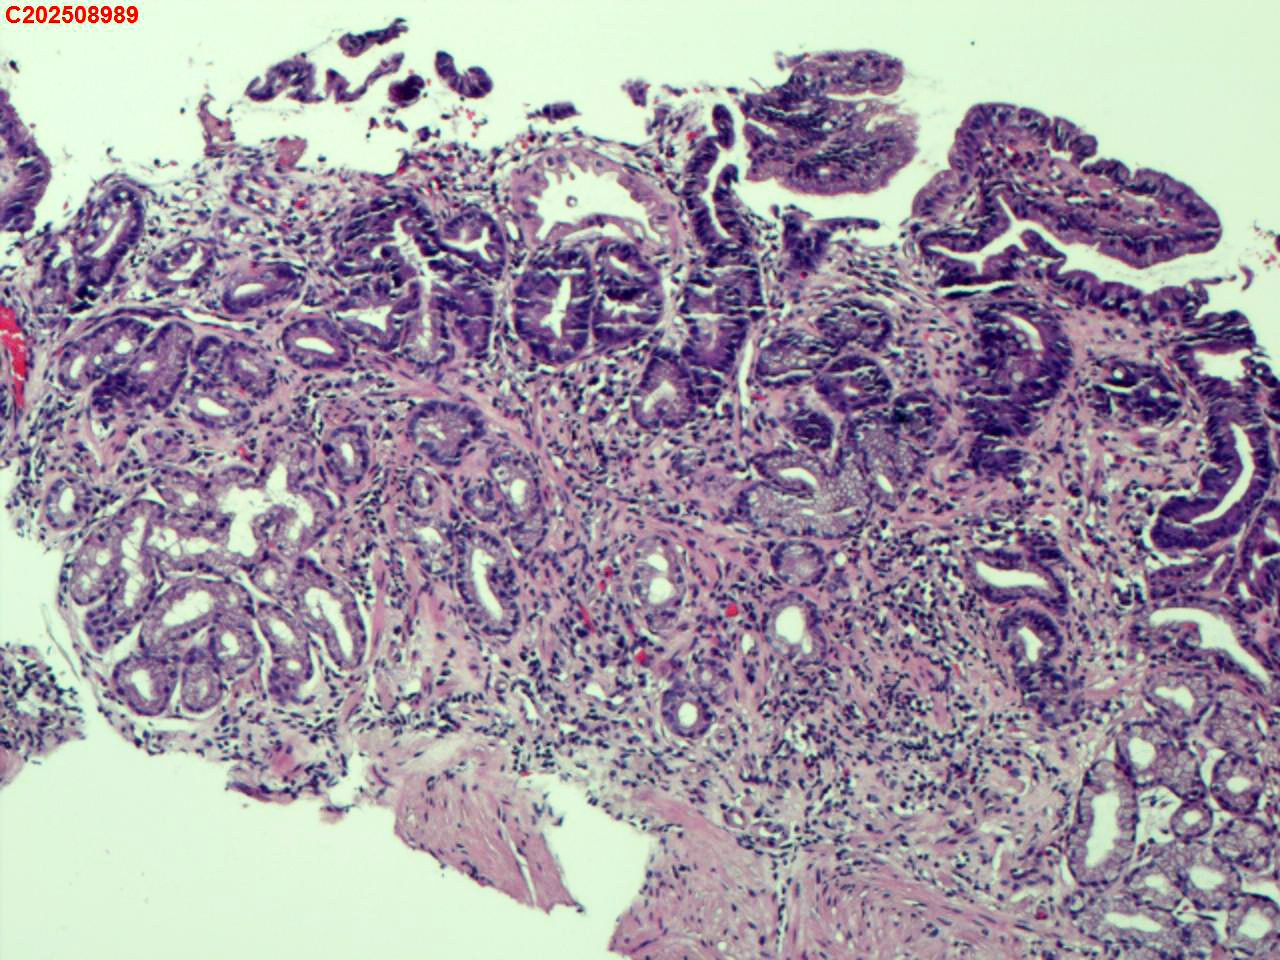

胃窦粘膜

性别

女

年龄

62岁

临床诊断

慢非萎伴糜烂

一般病史

体检

标本名称

大体所见

胃窦多发充血、糜烂。

萎缩+肠化+糜烂+修复

萎缩及糜烂

慢性萎缩性炎,伴肠化。